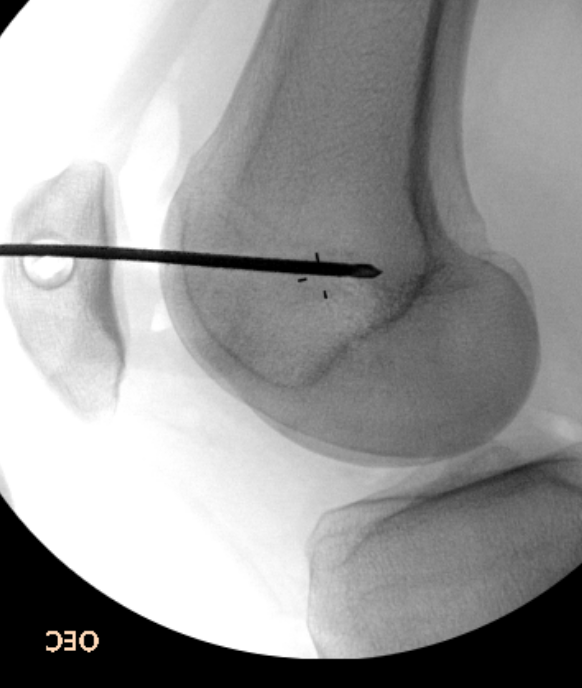

1. Arthroscopic lateral release

- knee in extension

- camera in AM portal

- hook diathermy in AL portal

- 5mm lateral to patella / 1cm superior to patella / down to anterolateral portal

- release retinaculum under vision

- must ensure SLGA coagulated / can visualise

- let down tourniquet at end of procedure

- ensure can evert patella 90o at end